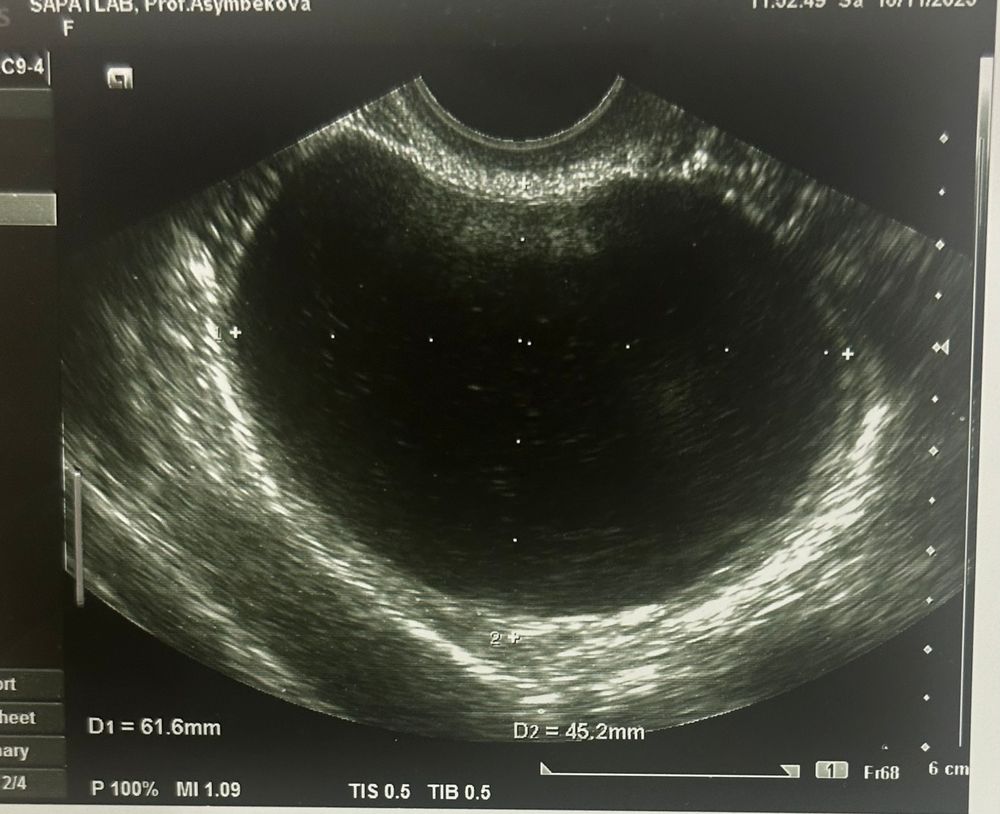

Всем привет. 4 месяца назад на узи обнаружили кисту размерами 6*5 см. Сказали что фолликулярная, назначили лечение. На следующий цикл киста совсем не изменилась, и по сей день она не уменьшилась ни на миллиметр. Что это может быть за киста? У кого было что-то подобное?

Планирую беременность, и не знаю что делать с этой кистой, АМГ и так низкий ( 1,9) после удаления кисты наверное вообще упадет

Если образование в яичнике не уходит в течение 3х циклов , то делаем мрт. Дифференциальная диагностика с серозной цистаденомой.

Разница на узи в толщине стенки. На обычном аппарате не углядеть. Можно экспертное узи сделать. Но золотой стандарт -мрт. Плюс, сдать на онкомаркеры (са125, he4)

В течение 3х месяцев уже должно было что-то произойти с кистой. Но большие фолликулярные кисты могут существовать до 6 месяцев . потом требуется оперативное лечение и гистологическое исследование .